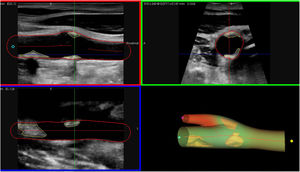

Por último, resaltar los avances tecnológicos en ecografía carotidea 3D, que permiten cuantificar con mayor precisión y en menor tiempo el volumen de la placa aterosclerótica (fig. 2), facilitando así la estratificación del riesgo cardiovascular incluso en las fases más tempranas de la enfermedad43.